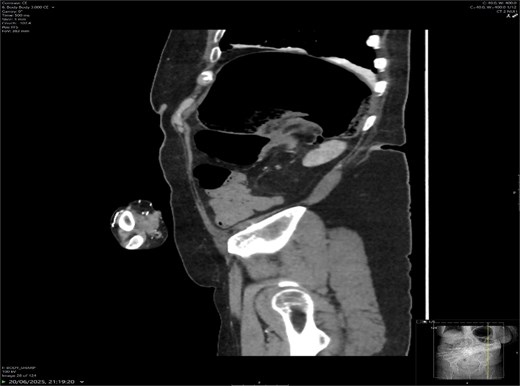

A contrast-enhanced CT scan of the abdomen demonstrated a whirl sign at the mesenteric root (Figs 1 and 2), dilated transverse colon with a transition point at the splenic flexure (Fig. 3), and no evidence of ischemia or perforation (Fig. 4). These findings were consistent with TCV.